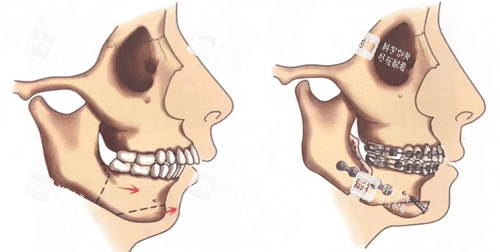

小牛的故事,堪称“颌面逆袭教科书”。她从小因上颌发育过度、下巴后缩被同学起外号“月亮脸”,工作后因形象自卑不敢参加社交活动。2024年初,她找到艾伟健医生,经过详细评估后,医生制定了“上下颌根间截骨术+颏成型术”方案。术后3个月复查时,她的脸型从“凸面型”变成流畅的“直面型”,连同事都追问“是不是偷偷去做了医美”。

术前精细建模:通过CT扫描和3D数字建模,提前模拟手术路径,避免神经损伤;

术中小创口操作:内窥镜辅助下,切口藏在口腔内,术后不留疤;